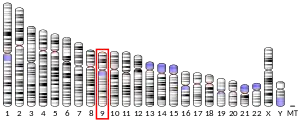

Complement component 5 is a protein that in humans is encoded by the C5 gene.[5]

- Wetsel RA, Lemons RS, Le Beau MM, et al. (1988). "Molecular analysis of human complement component C5: localization of the structural gene to chromosome 9". Biochemistry. 27 (5): 1474–82. doi:10.1021/bi00405a012. PMID 3365401.